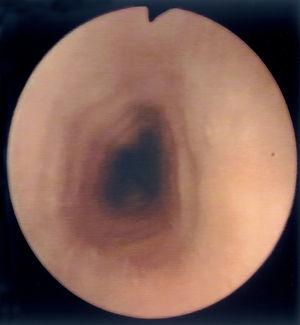

Al estudio endoscópico, en 2 pacientes (18,18 %) se observó una pérdida del patrón circular normal y tendencia a la traquealización (aspecto corrugado y patrón triangular con escasa insuflación) (fig. 1). En otros 2 pacientes se observaron lesiones puntiformes de aspecto blanquecino que correspondieron a acumulaciones de eosinófilos en el estudio histológico (figs. 2 y 3) y en un paciente se observó discreto prolapso cardial. En los otros 6 pacientes los resultados macroscópicos eran normales.

Figura 1.Aspecto corrugado o "traquealización" del esófago, hallazgo característico de esofagitis eosinofílica. El aspecto de anillos transversales se corresponde con contracciones intermitentes de la capa muscular circular.

En cuanto a los hallazgos endoscópicos pueden ir desde un aspecto de la mucosa esofágica estrictamente normal a diferentes patrones de alteración endoscópica. Se ha descrito la existencia de imágenes erosivas longitudinales, granularidad, pérdida del patrón vascular, estenosis focales6, estenosis de larga extensión ("esófago de pequeño calibre")17 y fragilidad mucosa de fácil erosión al contacto con el endoscopio (denominado como crêpe paper esophagus)18. Pero el patrón que se ha comunicado con más frecuencia es el de traquealización esofágica, denominado de este modo por la presencia de imágenes de anillos transversales consecutivos que recuerdan el aspecto "corrugado" de la tráquea y que corresponderían a contracciones intermitentes de la musculatura circular esofágica19. Otra imagen bastante característica en estos pacientes es un punteado blanquecino que semeja el aspecto de candidiasis esofágica y que corresponde a acumulaciones o microabscesos constituidos por eosinófilos que protruyen sobre la superficie mucosa, como se demuestra por el estudio anatomopatológico20,21. En dos de nuestros pacientes se demostró este hallazgo.